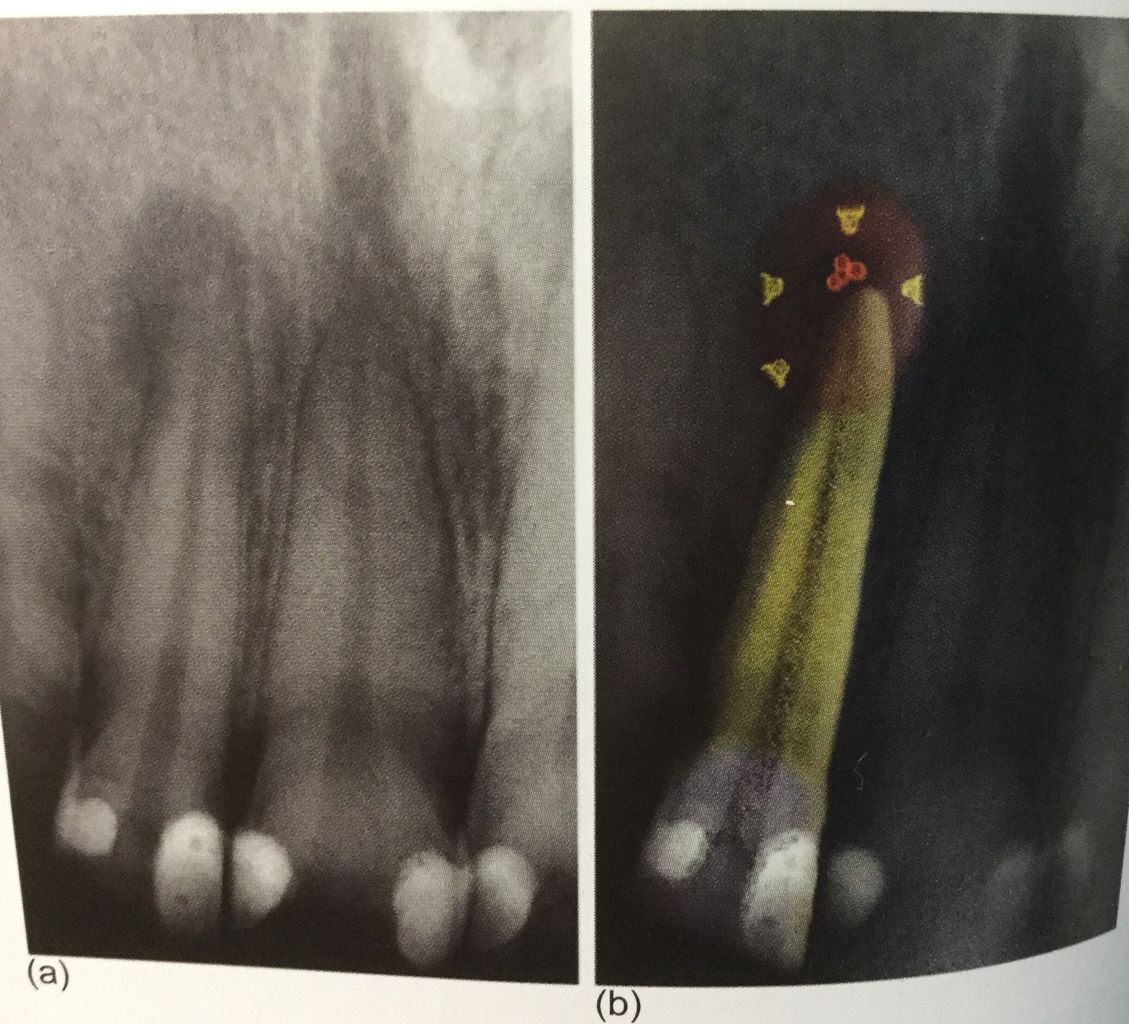

細菌が根の先にまで 進入してくると、

骨の細胞は細菌と戦えないんです。

一旦、骨がとけて肉芽って呼ぶ炎症性のお肉に変わります。

免疫細胞の中で好中球って細胞が死んだのが、膿なんです。

先日に書いたように完全に細菌を取り除くことはできません。

ので、外科的な治療が必要な歯もあるんです。